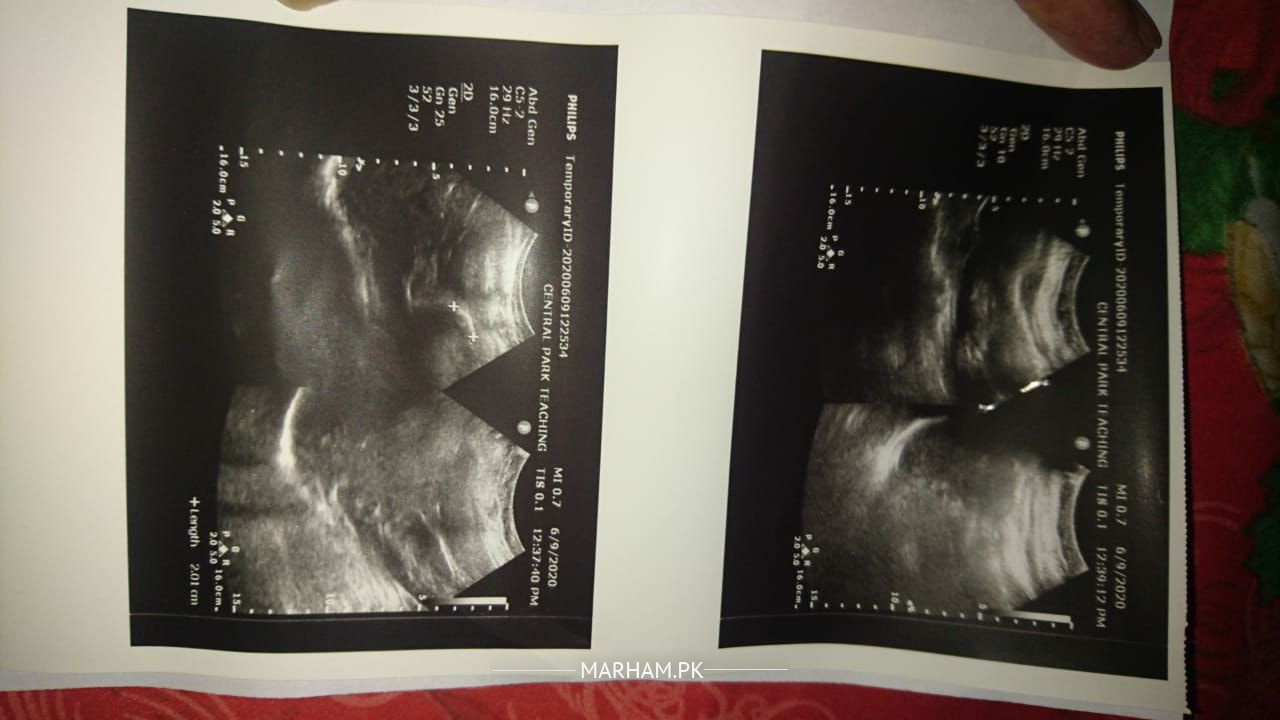

this abdominal ultrasound shows 3 stones in gallbladder..

rest of the report is fine..

Patient have gall bladder stone(pittay ki pathari)

stone in gall bladder

you are having cholilithiasis. yani pittay mai pathri hai.

the stone size is 21 mm which is considerably large and can cause blockage of duct as well.